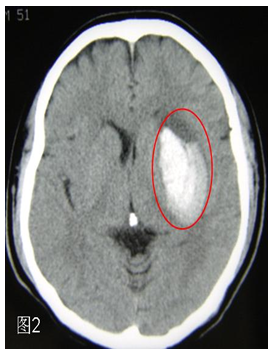

(1)首先应该做头颅CT

在某些地方也把头颅CT更形象地称作“脑扫描”。CT可以在最快的时间内了解,因为脑动脉堵塞而发生了脑梗死还是脑动脉破裂而出现了脑出血。脑梗死时头颅CT发现在脑组织出现了片状的黑色图像(图1),脑出血时可见在脑组织中出现了白色的团块(图2),一目了然。所以,得了脑卒中,第一要做的检查就是头颅CT。